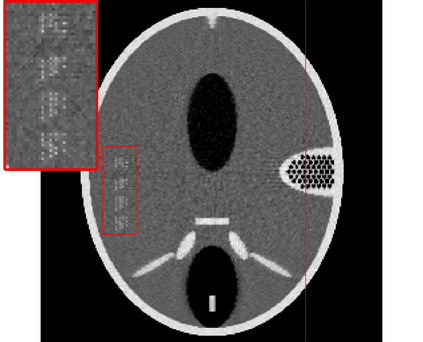

In the classic sparsity-driven problems, the fundamental L-1 penalty method has been shown to have good performance in reconstructing signals for a wide range of problems. However this performance relies on a good choice of penalty weight which is often found from empirical experiments. We propose an algorithm called the Laplacian variational automatic relevance determination (Lap-VARD) that takes this penalty weight as a parameter of a prior Laplace distribution. Optimization of this parameter using an automatic relevance determination framework results in a balance between the sparsity and accuracy of signal reconstruction. Our algorithm is implemented in a transmission tomography model with sparsity constraint in wavelet domain.